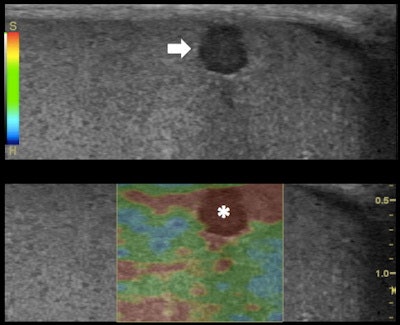

Top: Grayscale ultrasound longitudinal image of the testes: subcapsular 3-mm (in size) hypoechoic lesion (arrow). Bottom: RTE shows higher tissue displacement of the lesion (displayed in red) (*) compared with the testicular tissue (mainly displayed in green), suggesting a benign appearance: dense cyst. All images courtesy of Dr. Alfredo Goddi, SME-Diagnostica per Immagini Medical Center, Varese, Italy.

RTE evaluates the relative elasticity of different tissues by using a fast cross-correlation technique and a combined autocorrelation method. It creates an elastogram that is superimposed to the B-mode ultrasound image of the tissue and updated in real-time. The elastograms display a color-coded map of the relative elasticity -- stiffer areas are depicted as blue and softer areas are red; green indicates an intermediate level of elasticity.